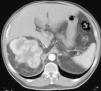

Objetivo. El oncocitoma es un tumor renal benigno, relativamente infrecuente. Hasta este momento su diferenciación radiológica del carcinoma de células renales se considera imposible, aunque hay escasos artículos en que se haya utilizado la tomografía computarizada (TC) trifásica. Los autores describen los hallazgos con TC trifásica en estos tumores, valorando si algunas características, aunque no diagnósticas, sí pudieran sugerir la posibilidad de este diagnóstico. Esto, en algunos casos, podría cambiar el manejo de los pacientes. Material y métodos. Se describen los hallazgos de TC trifásica en 10 casos de oncocitoma, vistos en 8 pacientes (un caso era multifocal-bilateral). En todos los casos el diagnóstico fue anatomopatológico, en la pieza de resección. Resultados. Todos los tumores fueron hallazgos ecográficos incidentales previos a la TC, presentando un tamaño muy variable, de 3 a 15 cm, con una media de 5,2 cm. El contorno era bien definido. Uno de los pacientes tenía tumores bilaterales (2 derechos y 1 izquierdo). Excepto en un tumor, el resto mostraban una cicatriz «estrellada» interna, que en un caso seguía un marcado patrón lobular. La captación tumoral de contraste fue ávida, con una media de 120 HU en fase arterial y 116 HU en fase excretora. La evolución de todos los pacientes fue buena, no detectándose recidivas postquirúrgicas. Conclusiones. Aunque la diferenciación con el carcinoma de células renales no puede hacerse con certeza, debe sugerirse la posibilidad de oncocitoma, fundamentalmente en tumores pequeños, con cicatriz central, ausencia de necrosis, falta de infiltración y un patrón de captación como el que se describe. Independientemente del tamaño, una morfología lobular del tumor también debe sugerir esta posibilidad.

Objective. Oncocytoma is a relatively uncommon benign kidney tumor. To date, it has been impossible to differentiate this tumor from renal cell carcinoma radiologically, although few articles report on the use of tri-phase CT in this tumor. We describe the triphasic CT findings in these tumors and evaluate whether some characteristics, although not sufficient to ensure the diagnosis, can suggest the possibility of oncocytoma. In some cases, this may lead to a different approach to the management of patients. Material and methods. We describe the tri-phase CT findings in 10 cases of oncocytoma in eight patients (one case was bilateral and multifocal). The diagnosis was made after histological examination of surgical specimens in all cases. Results. All the tumors were found incidentally at ultrasound examination prior to CT study. Tumors all had well-defined borders, and their size ranged from 3 to 15 cm, with a mean diameter of 5.2 cm. One patient had bilateral tumors (2 right and 1 left). All but one of the tumors had a star-shaped scar inside, with a marked lobular pattern in one case. All tumors showed avid uptake, with mean enhancement of 120 HU in the arterial phase and 116 HU in the venous phase. All patients evolved favorably with no post-surgical relapse. Conclusions. Although oncocytoma cannot be differentiated from renal cell carcinoma with certainty, the possibility of oncocytoma should be suggested in the case of small tumors with a central scar, without necrosis or infiltration, and an enhancement pattern as described here. Regardless of the size of the tumor, lobular morphology should also suggest this possibility.